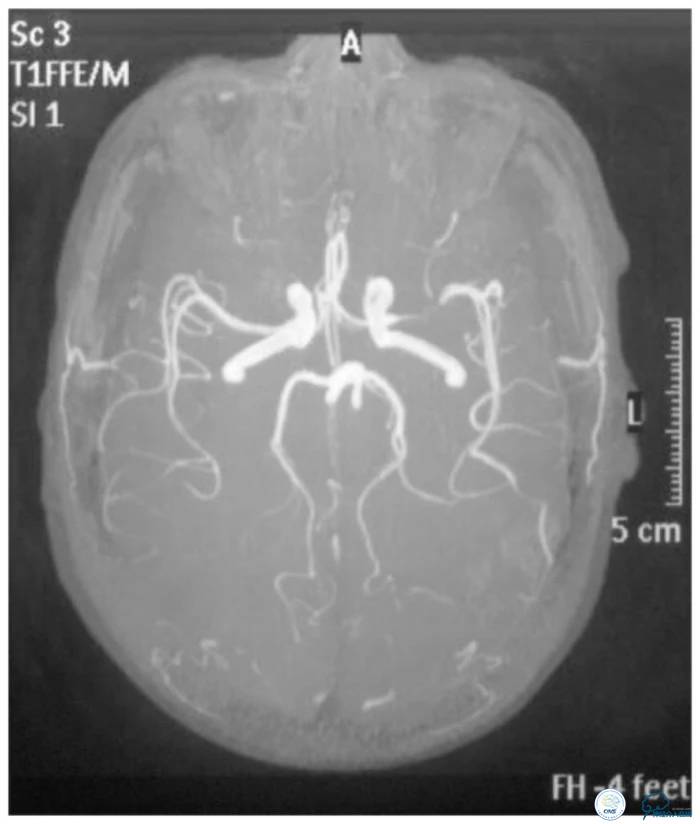

MRA示左侧大脑中动脉狭窄(图4)。

图4

CTA:左大脑中动脉水平段狭窄(图5)。

图5